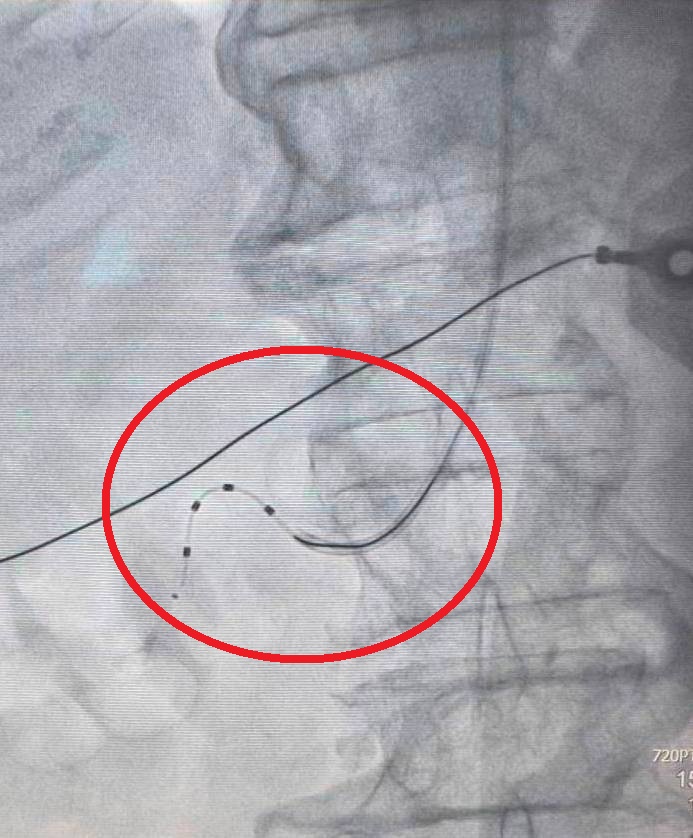

導管腎臟交感神經阻斷術是一種用於治療高血壓的導管介入技術,需從手或腳打針將導管放入血管,再給予低電量射頻,以降低兩側腎交感神經活性,促使病人的收縮壓下降10~40mmHg,並達到長期穩定控制血壓的目的。

大千綜合醫院心臟內科醫師羅健賢表示,李女士在接受一個月的藥物治療後,血壓仍然難以控制,加上已使用多達7種的降血壓藥,狀況還是不甚理想,因此建議其接受導管腎臟交感神經阻斷術治療。病人術後隔天即出院,門診追蹤血壓狀況逐漸穩定並逐步減少藥物,術後兩個月只剩三種降血壓藥物,且服藥次數也減少為每日一次。三個月後以24小時血壓測量檢查,確認血壓呈現穩定。